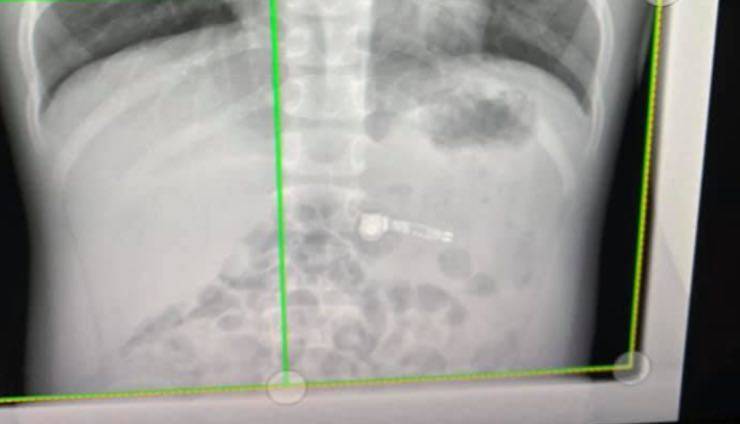

Le fotografie postate da Kiara Stroud, nome della mamma dei bimbo, mostrano l’aggeggio elettrico incastrato nell’addome del bambino.

Un bambino di soli 7 anni ha dunque ingoiato le AirPod e sua madre, Kiara Stroud, ha postato le foto delle lastre sulla sua personale pagina Facebook. Immediatamente sono arrivati per la donna tantissimi messaggi di solidarietà e, fortunatamente il piccolo è ora fuori pericolo.